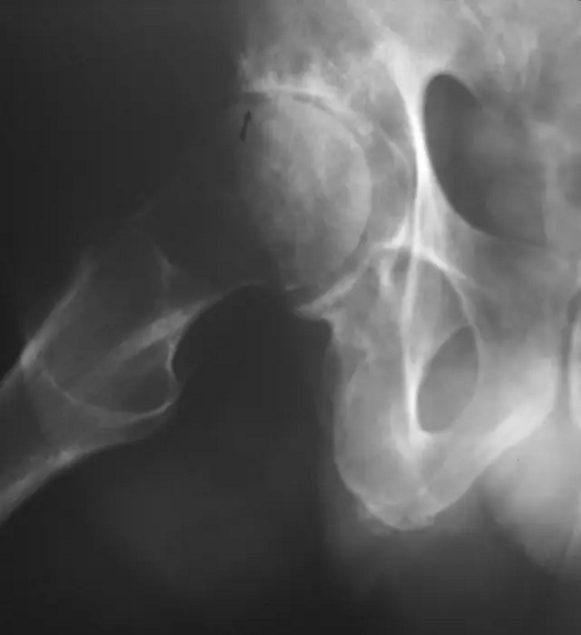

患者的臀部的蛙式位图片,新月征显示缺血坏死志,表明软骨下骨折。 一旦出现这种迹象,治疗性干预就不太可能阻止疾病的进展。新月征是指股骨头负重区软骨下骨板内1~2mm厚的透光区,是由于骨坏死后,骨质被吸收,出现微骨折所致,通常在正位片上不易见到,在蛙式位片上易显示,容易被忽视。

股骨头缺血坏死X线片显示新月征